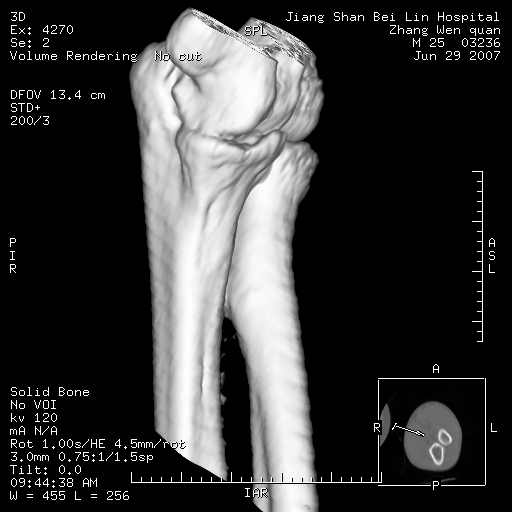

标题: CT8866:男27岁,正常吗?

患者男27岁,2007年3月查出患上肘关节滑膜结核,此后行手术滑膜剥除,今查ct

看一下上面的桡骨粗隆有问题吗?

桡骨粗隆有问题,术后改变

桡骨骨皮质破坏,结合病史考虑结核